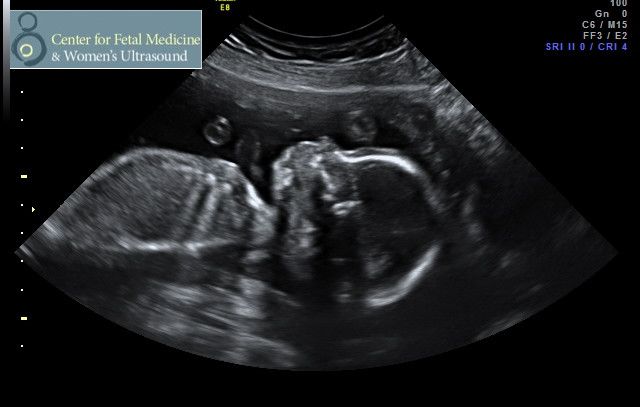

But on the really BRIGHT side, we had our 20-week ultrasound a few weeks ago (we’re now officially 23 weeks and counting!) and got an enthusiastic two thumbs up from the imaging doc, who has seen literally tens of thousands of babies – Ella is structurally awesome, weighs in right on track, and is as cute as an ultrasound baby can be ;)